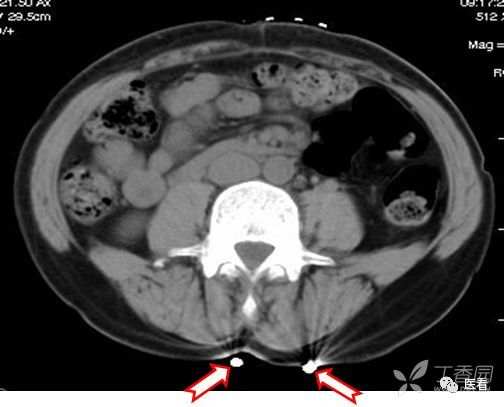

CT造影中可能出现的假象——涡流

这里强调一个CT造影中可能产生的假象——涡流

也就是团注(高压注射器快速注入)的碘对比剂与血液没有混匀之前,没有对比剂的血液呈低密度(红箭头),有对比剂的血流呈高密度,不要误认为是血栓